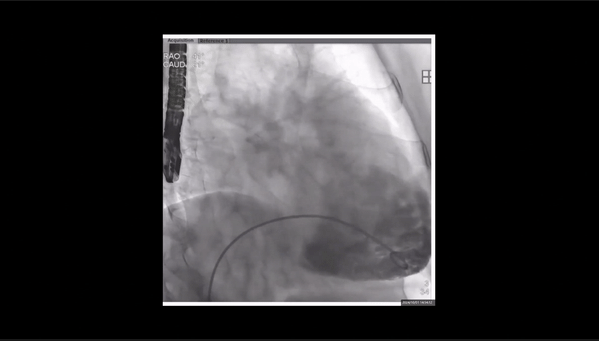

術(shù)前右室造影

夾持件位置確認(rèn)

室間隔位置確認(rèn)